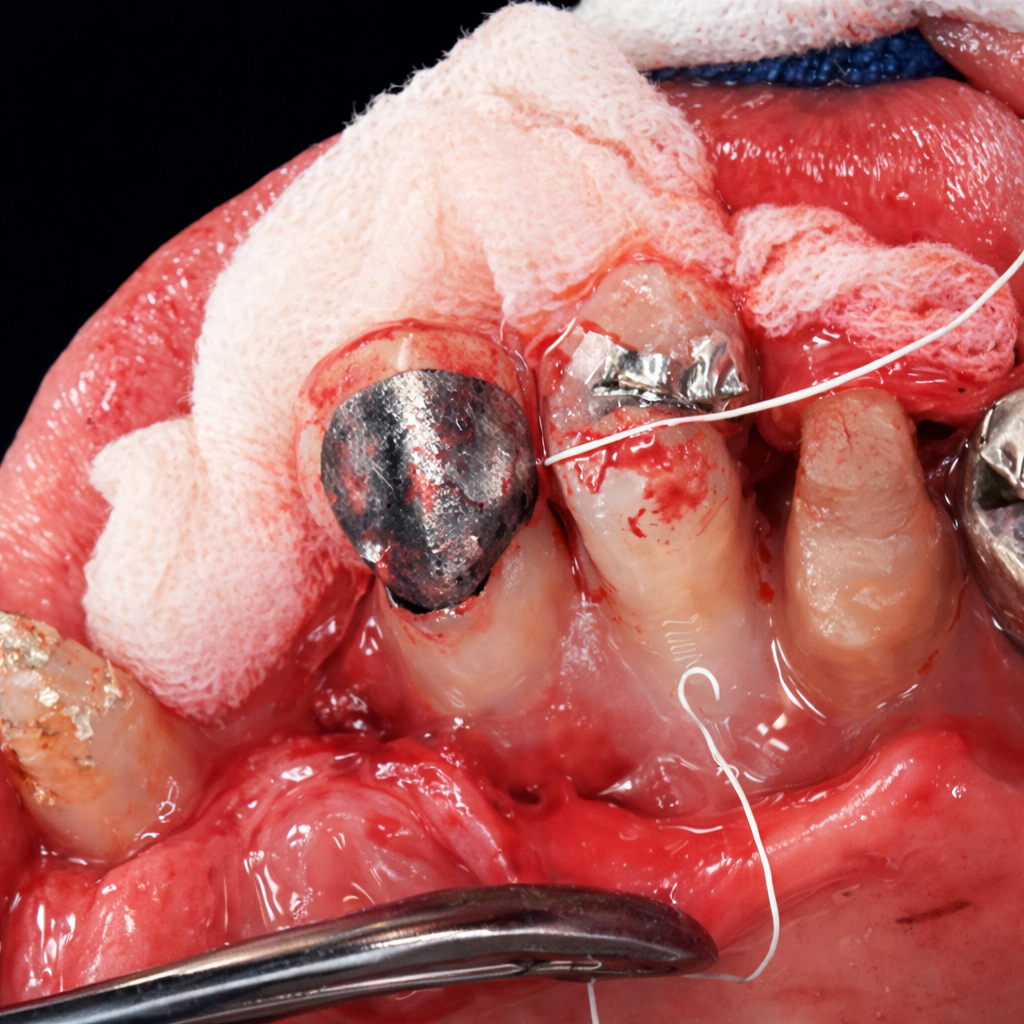

午前-45

67識の女性。上顎左側小臼歯の動揺を主訴として来院した.上顎左側 第一小臼歯の近心に深い歯周ポケットを認めた。歯周基本治療後、同部位にエナメルマトリックスタンパク質を用いた歯周外科処置を行うこととなった。 初診時のエックス線画像と不良肉芽組織除去後および縫合直前の口腔内写真を別に示す。

この手術で再生するのはどれか。2つ選べ。

a.歯槽骨

b.象牙質

c.エナメル質

d.セメント質

解答を見る

a.d